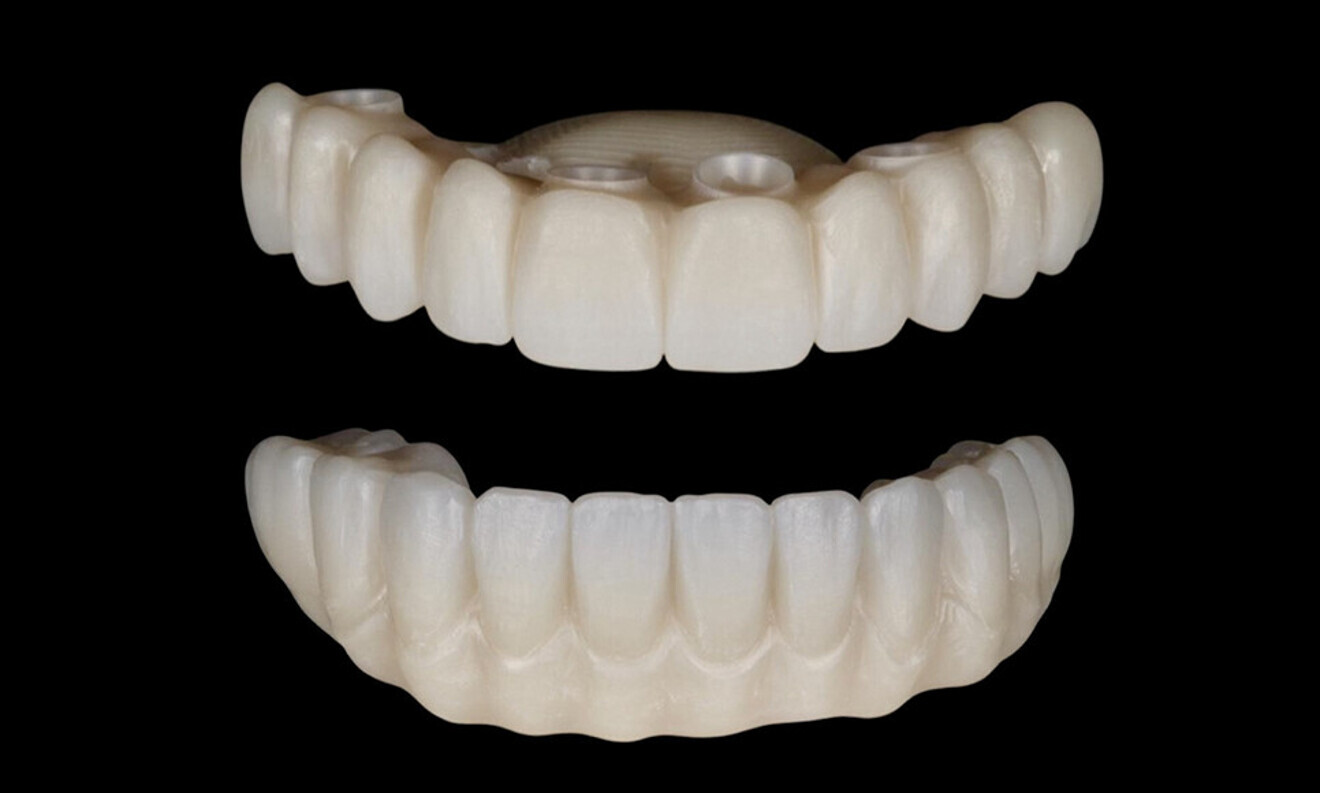

After a healing period of five months and successful osseointegration, the process for the definitive restorations was initiated. The chosen material was milled monolithic zirconia, and Variobase final abutments was used, placed on the screw-retained abutments to ensure excellent stability and retention of the definitive restorations (Figs. 69–75).

Figs. 69–75: The definitive restorations were fabricated after a five-month healing period

The soft tissue was in good condition, and the definitive restorations were placed (Figs. 76 & 77). After placing the definitive restorations, oral hygiene instructions were given to ensure proper care and prevent complications. Additionally, the occlusion was carefully checked and adjusted as needed (Figs. 78–83).

Figs. 78–82: The definitive restorations were placed, and occlusal adjustments were performed.

Fig. 83: The definitive restorations were placed, and occlusal adjustments were performed.